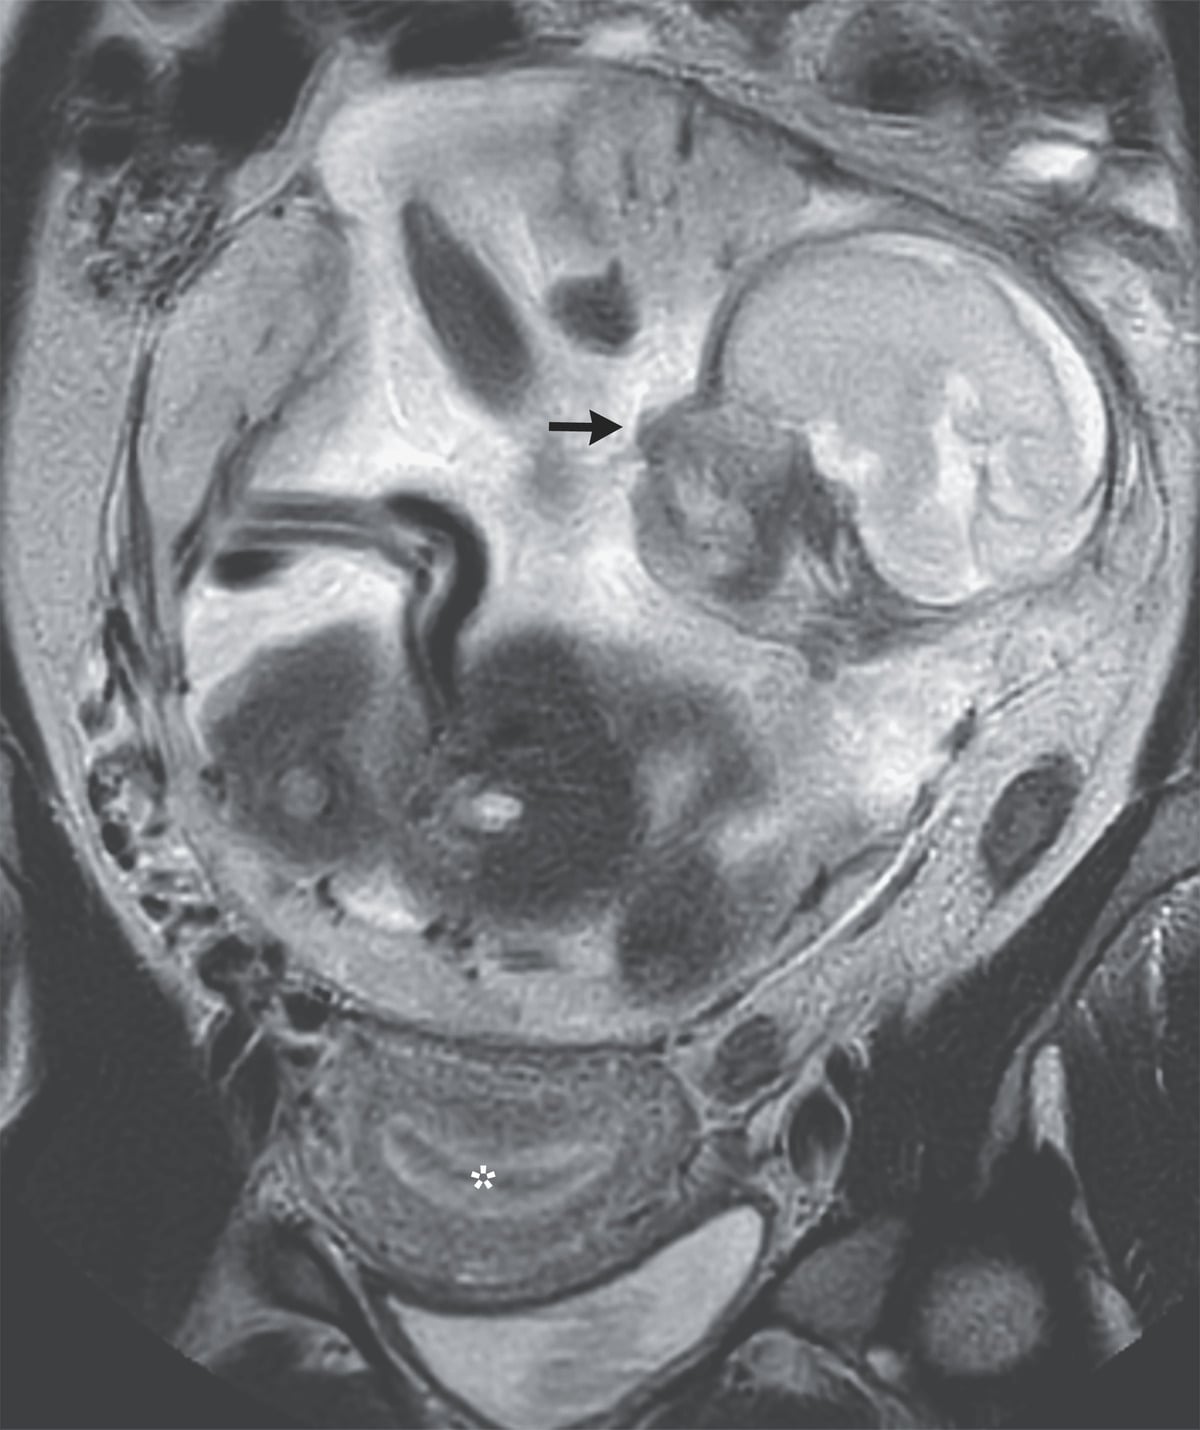

Statystyki wskazują, że aż 97 proc. przypadków ciąż pozamacicznych występuje w jajowodzie, zaledwie 2 proc. w jajniku lub szyjce macicy. Mniej niż 1 proc. przypadków stanowi ciąża pozamaciczna w jamie brzusznej, między narządami wewnętrznymi. Rosnący zarodek podrażnia błonę wyścielającą jamę brzuszną i może doprowadzić do uszkodzenia narządów wewnętrznych. Takie przypadki są ekstremalnie rzadkie, nawet w literaturze medycznej. Ryzyko utraty dziecka szacuje się na ok. 90 proc., a u maluchów które przeżyją poród ryzyko wystąpienia wad wrodzonych lub uszkodzenia mózgu wynosi 1 na 5.

Mimo wszystkich przeciwności losu, lekarzom z Francji udało się doprowadzić ekstremalną ciążę do rozwiązania w 29. tygodniu. Co prawda, matka i dziecko musiały przez dość długi czas być na szpitalnej obserwacji, ale po trzech miesiącach wypisano ich do domu. Kobieta ma już dwójkę dzieci, a wcześniej przeżyła poronienie.